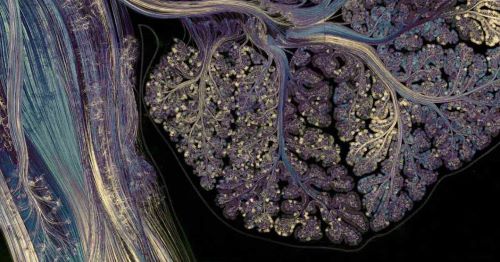

At first glance, the cerebellum looks a bit like a wrinkly, overgrown walnut shell. A closer look reveals two hemispheres with creases on the surface that sink down into deep grooves and split off into a network of coral-like branches. Peering through a microscope reveals a uniform pattern of densely packed cells. The cerebellum makes up only about 10 percent of the mass of the human brain, but contains more than half of its neurons. Stretched out, its surface area would be nearly 80 percent that of the cerebral cortex.